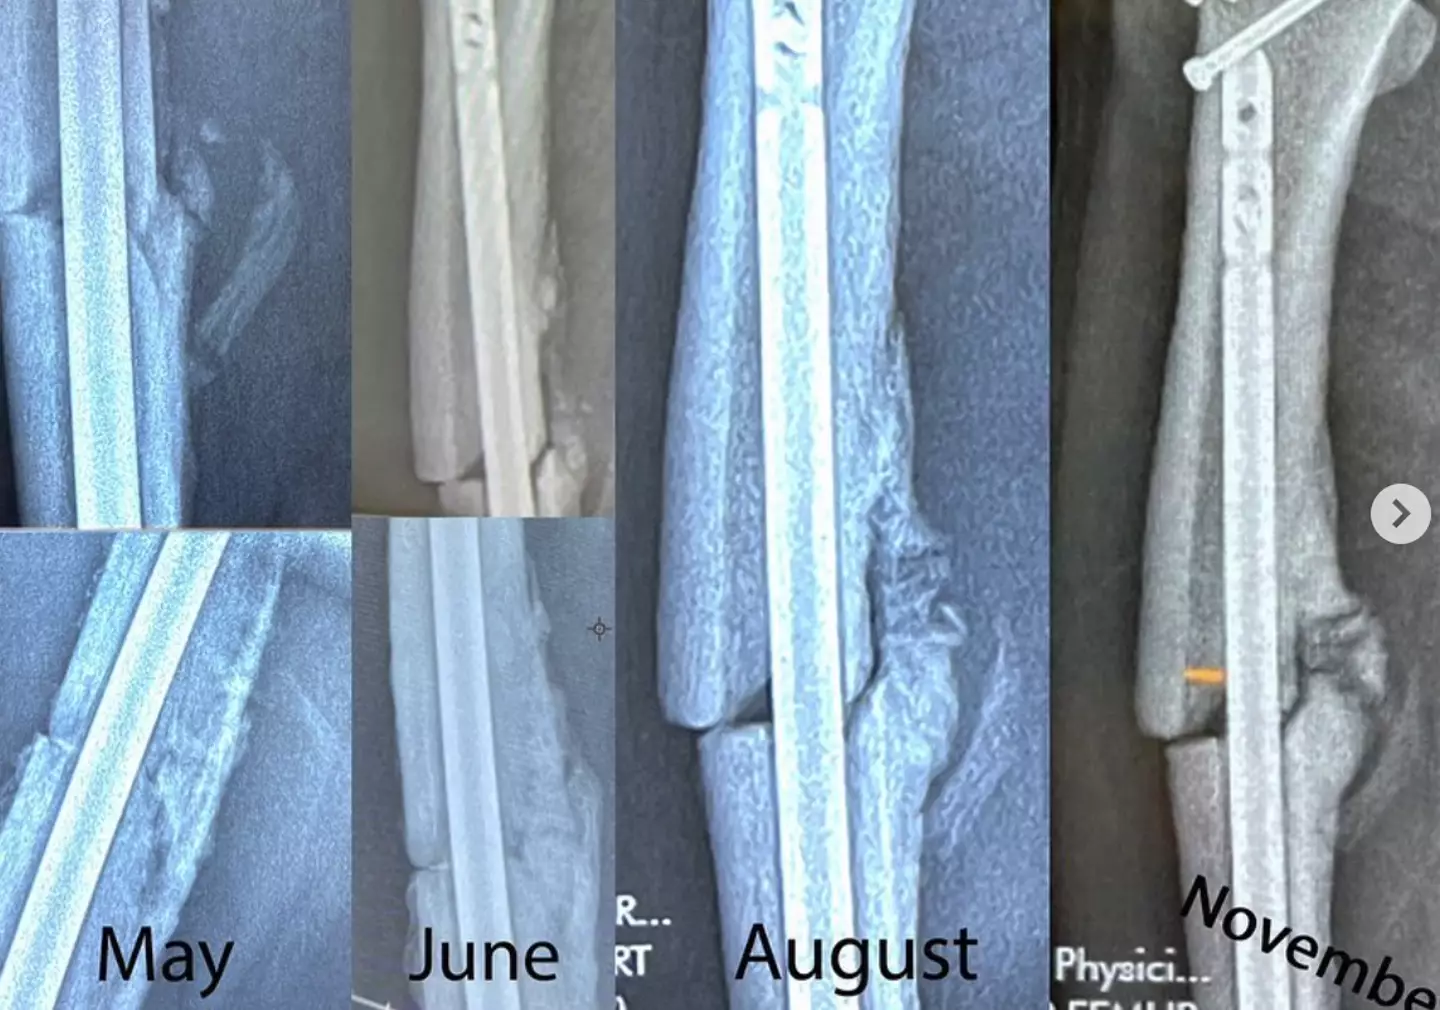

Hawk wrote: "I was dreaming when I wrote this, forgive me if it goes astray: last week I got confirmation of news that I have been dreading for while now: my femur never fully connected at the fracture site (non-union and varus angulation as they say in the biz) and has only grown further apart on one side of my leg.

"I was too cavalier in my approach to skating shortly after my injury, ignoring all warning signs - pain, mostly - and ended up shifting the bone placement that never allowed it to fuse properly.

He continued: "So I go back in for surgery next week to have my bone repositioned in hopes that it will heal properly this time around.

"I am thankful to get a 'do-over' of sorts, and hopeful that I can make a fuller recovery this time by having more patience and less expectations. "The silver lining to this disappointing news is that I was able to do a lot of skating (and some advanced tricks) without a solid bone to stand on; I should be able to do a lot more with a fully formed femur.